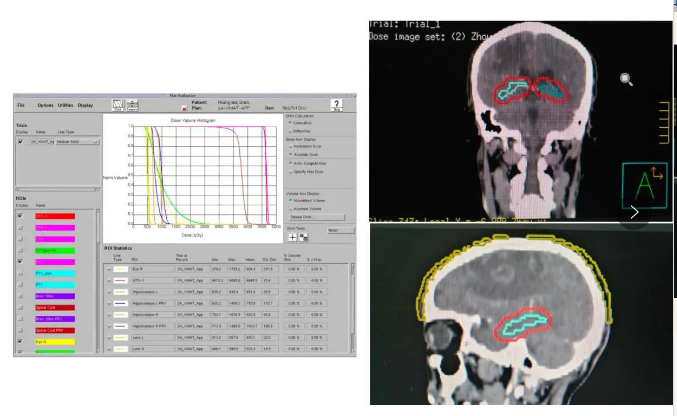

团队年肺癌放疗量在400例以上,常规开展3D-RCT、IMRT、VMAT等调强放疗技术,肺癌立体定向放射治疗(SBRT)在粤西首先开展,海马保护、毛囊保护的肺癌脑转移脑部放射治疗与中国科学院大学附属肿瘤医院合作完成,为国内较早开展。晚期肺癌年治疗4000人次以上,紧跟国内外指南规范地开展肺癌新辅助免疫联合化疗、辅助化疗和靶向治疗、姑息性靶向治疗、免疫治疗、抗血管生成治疗、肺癌脑转移放疗和肺癌全程管理等综合性治疗。参加多项国际、全国多中心肺癌临床研究,为广大患者提供使用新药的机会。

海马保护放疗新技术开展